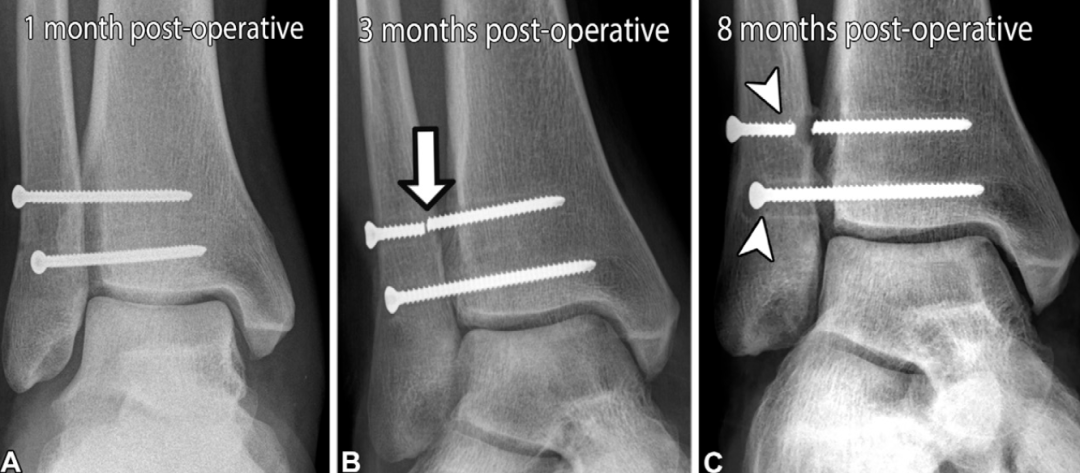

术后并发症

与术前评估相似,术后评估也主要依靠影像学表现:术后即刻影像学检查用于确认植入物位置和骨折复位效果;随访X线片则用于观察骨折愈合情况,确认胫腓联合复位的维持状态。当怀疑骨性不愈合或持续性不稳时,CT检查具有重要价值;当患者术后出现疼痛,尤其怀疑存在持续性韧带缺损和/或肌腱异常时,可采用MRI检查。约15%的患者会发生术后并发症,其中39%表现为胫腓联合愈合不良,多数病例由初始复位不足所致;4%的手术干预会发生感染并发症。

刚性螺钉固定带来的生物力学负荷,会引发多种并发症,包括胫腓联合复位不良、螺钉松动、螺钉移位和螺钉断裂,这些并发症均可能需要取出螺钉:

上述并发症可能无明显的临床症状,从而延误对疼痛性螺钉或持续性胫腓联合不稳的发现和干预。放射科医生需在影像学检查中识别这些异常并予以提示,但同时也应注意,若胫腓联合已实现良好的愈合复位,螺钉周围的松动或螺钉断裂可能无临床症状,甚至提示胫腓联合的生理活动已部分恢复。

缝线纽扣装置可能导致的并发症包括:固定稳定性不足或失效、结刺激、无菌性骨溶解和/或感染。缝线纽扣装置的取出率低于螺钉固定,这一特点也为其成本效益优于螺钉固定的观点提供了支持。

胫腓联合翻修手术最常见的指征为:初次固定后出现复发性分离或复位丢失。